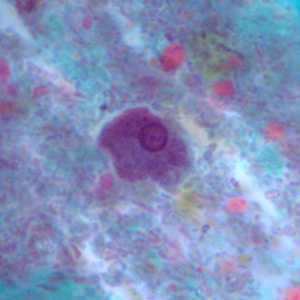

Figure A: Cyst of E. polecki stained with trichrome. Notice the large nucleus with a pleomorphic karyosome and numerous variably-shaped chromatoid bodies.

Figure B: Cyst of E. polecki stained with trichrome. Notice the large nucleus with a pleomorphic karyosome and numerous variably-shaped chromatoid bodies.

Figure C: Cyst of E. polecki stained with trichrome. Notice the large nucleus with a pleomorphic karyosome and numerous variably-shaped chromatoid bodies.

Figure D: Cyst of E. polecki stained with trichrome. Notice the large nucleus with a pleomorphic karyosome and numerous variably-shaped chromatoid bodies.

Figure E: Cyst of E. polecki stained with trichrome. Notice the large nucleus with a pleomorphic karyosome and numerous variably-shaped chromatoid bodies.

Figure F: Cyst of E. polecki stained with trichrome. Notice the large nucleus with a pleomorphic karyosome and numerous variably-shaped chromatoid bodies.